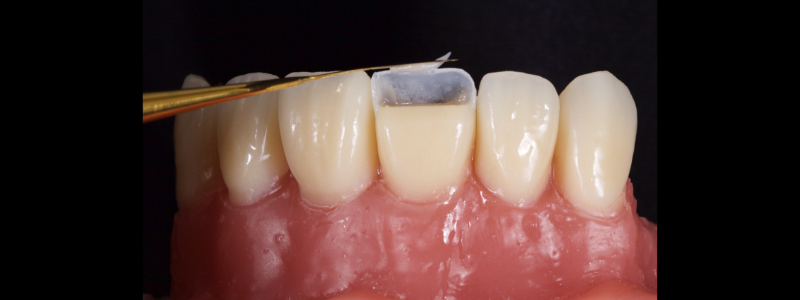

To achieve this, the achromatic enamel mass is first placed on a PVS Putty stent made from a diagnostic wax-up with a flat plastic (see the first article in this series for more detail). The enamel mass is thinned with a flat plastic in combination with a multipurpose condenser, a #3 brush (i.e., GC, Cosmedent, Tokuyama), and some modeling resin (Fig. 7).

A modeling resin is a liquid resin that does not contain HEMA — examples include modeling resin (Bisco), Brush and Sculpt (Cosmedent), and Signum (Kulzer). The unpolymerized resin is then carried in the stent to the tooth and adapted to the palatal margin with a #3 brush (Fig. 8).

Before polymerization, the contact points are cleared with an Interproximal Carver Long (IPCL) like American Eagle (Fig. 9). The resin mass is then polymerized to create a palatal shell (Fig. 10).

In this case, a 23-year-old male presented with Ellis Class II fractures of both central incisors (Fig. 23). He had no interest in closing his diastema or restoring the peg laterals. A treatment plan was agreed upon to restore both central incisors with direct resin.